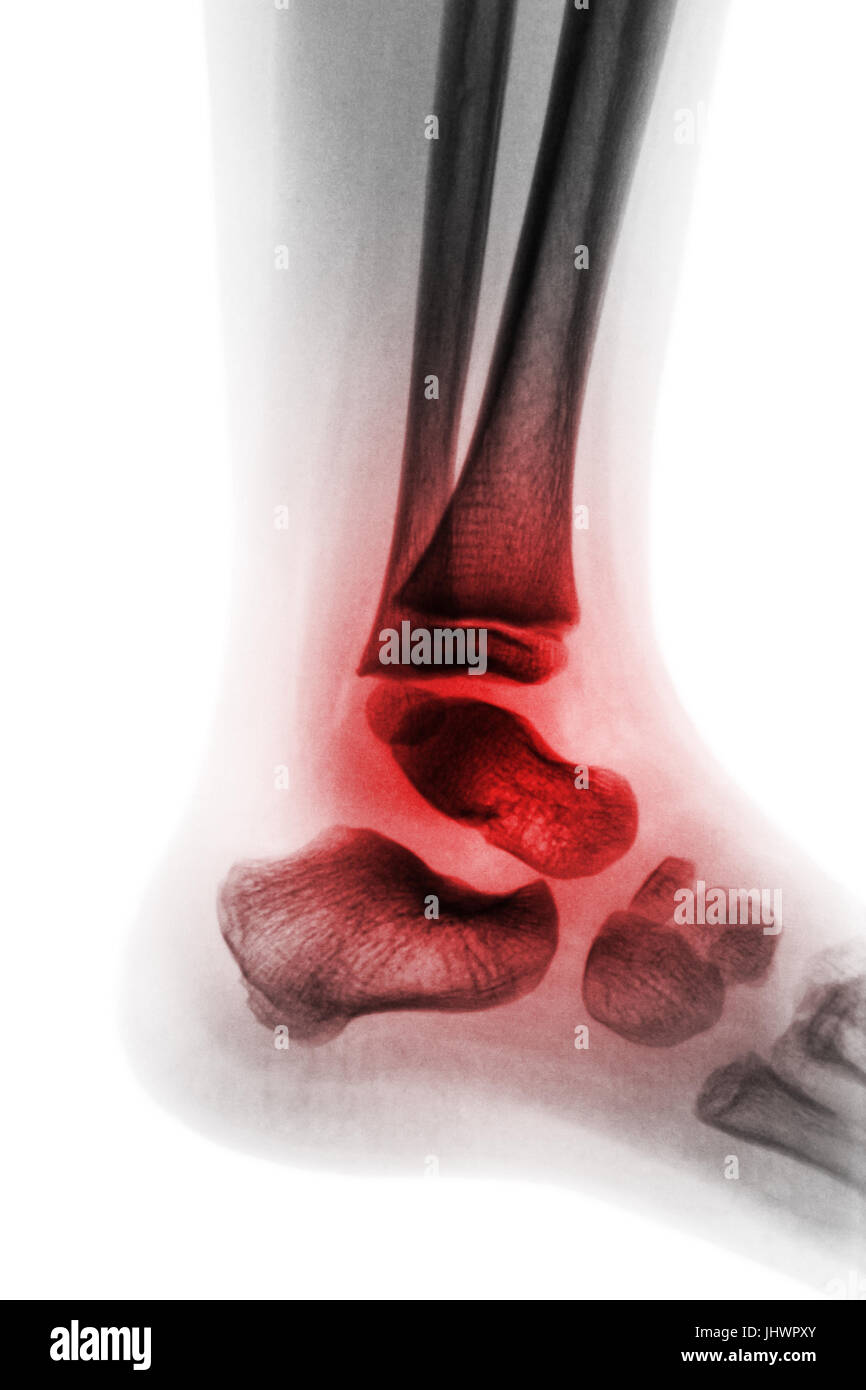

Osteoarthritis of the ankle, Xray Stock Image C019/4164 Science

Osteoarthritis of the ankle, Xray Stock Image C019/4164 Science Severe Arthritis In Ankle Xray The average age of the patient affected by ankle oa is around 50 years, being therefore active patients and in working age. The most severe feature(s) of the osteoarthritis, such as joint space narrowing. Most commonly caused by post. They are the most valuable additional test for. Osteoarthritis (oa) of the ankle is the progressive damage to the articular surface. Severe Arthritis In Ankle Xray.

Osteoarthritis of the ankle, Xray Stock Image F008/3482 Science Severe Arthritis In Ankle Xray They are the most valuable additional test for. Ankle arthritis is a common degenerative joint disease of the tibiotalar joint that presents with pain, stiffness, and deformity of the ankle. Osteoarthritis (oa) of the ankle is the progressive damage to the articular surface of the ankle joint including cartilage and subchondral bone which usually leads to pain joint. Most commonly. Severe Arthritis In Ankle Xray.

Ankle osteoarthritis, Xray Stock Image C053/3908 Science Photo Severe Arthritis In Ankle Xray Most commonly caused by post. Osteoarthritis (oa) of the ankle is the progressive damage to the articular surface of the ankle joint including cartilage and subchondral bone which usually leads to pain joint. Any varus/valgus deformity, and if such, the degree. Narrowing of the joint space between bones (a sign of cartilage loss), changes in the bone (such as fractures). Severe Arthritis In Ankle Xray.